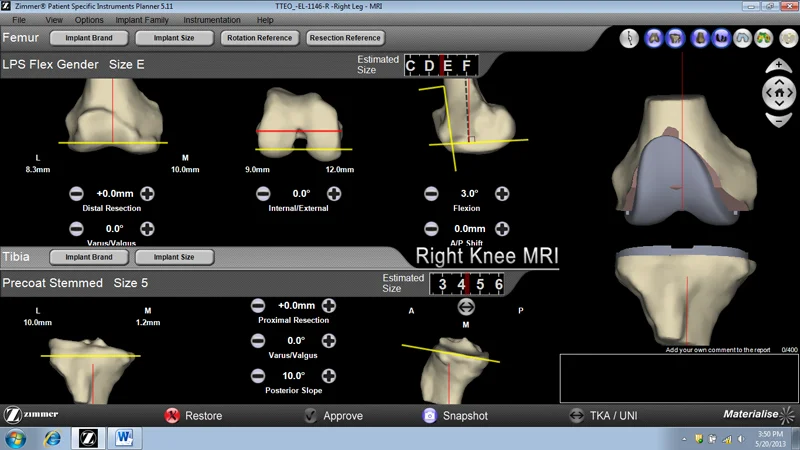

Mới: Phẫu thuật tạo hình khớp gối với sự hỗ trợ của máy vi tính

Phẫu thuật tái tạo khớp gối theo phương pháp ít xâm lấn đã giúp cải thiện tính thẩm mĩ, mất máu ít hơn, ít đau và phục hồi chức năng nhanh hơn. Tuy nhiên trong phẫu thuật có thể xảy ra khả năng vị trí cấy ghép không chính xác và lượng ximăng không đủ dẫn đến thất bại. Để khắc phục vấn đề này, bác sĩ Victor Seah, chuyên gia về phẫu thuật chỉnh hình tại Bệnh viện Raffles Singapore đã kết hợp giữa phẫu thuật xâm lấn tối thiểu với sự hỗ trợ giúp điều chỉnh hướng của máy vi tính trong khi thực hiện ca phẫu thuật tái tạo khớp gối. Bác sĩ Victor Seah chia sẻ: “Phẫu thuật thay khớp gối dưới sự hỗ trợ của máy vi tính là phương pháp mới đang được áp dụng tại bệnh viện Raffles với nhiều lợi ích rõ rệt và tỷ lệ thành công trên 95%. Kỹ thuật mới này giúp giảm kích thước của sẹo từ 18 – 20 cm theo phương pháp truyền thống xuống nhỏ hơn 12 cm. Trong suốt quá trình phẫu thuật, các cơ được tách ra thay vì bị cắt nhằm giảm thiểu tối đa tổn thương lên các mô”.

Vai trò của máy vi tính trong phẫu thuật khớp gối là gì?

Một trong những mục đích chính của thay khớp gối toàn phần là làm thẳng chi dưới, bao gồm việc thiết lập lại trục cơ học trung tính. Trục này được tiếp cận bởi phim chụp tia X như một đường thẳng bắt đầu đi từ trung tâm của khớp háng, qua trung tâm của khớp gối đến trung tâm của mắt cá chân. Trong quá trình phẫu thuật khớp gối, bác sĩ phẫu thuật không thể trực tiếp xác định vị trí trung tâm của khớp háng, do đó bác sĩ sử dụng các đồ gá lắp đặc biệt để gián tiếp xác định vị trí điểm này. Tuy nhiên, do sự biến đổi giải phẫu ở những bệnh nhân khác nhau, độ không chính xác có thể lên đến 40% bệnh nhân. Do vậy việc cấy ghép khớp gối có thể không chính xác. Nếu vị trí cấy ghép lớn hơn 3 độ so với dự định thì nguy cơ thất bại của ca cấy ghép cao. Để tránh điều này, máy vi tính giúp điều chỉnh hướng trong phẫu thuật tạo hình khớp gối đã được phát triển.

Máy vi tính điều chỉnh hướng liên quan đến việc chèn đinh kim loại vào xương đùi và xương chày. Đinh này là vật phản xạ cho phép máy ảnh hồng ngoại xác định vị trí của các đinh trong không gian ba chiều. Một khi các đinh này được đặt, các bác sĩ phẫu thuật sẽ đặt một số điểm giải phẫu xung quanh đầu gối mà máy tính sau đó sẽ phân tích và có thể xây dựng một mô hình ba chiều của xương khớp gối trong thời gian thực. Các máy tính sau đó có thể giúp bác sĩ phẫu thuật cắt xương trong ca phẫu thuật, lựa chọn kích thước chính xác cần cấy ghép cũng như hỗ trợ cấy ghép chính xác. Bác sĩ phẫu thuật được hướng dẫn và hỗ trợ bởi các máy vi tính chứ không phải là đồ gá lắp thông thường, thanh kim loại không được đưa vào trục của xương đùi và xương chày. Điều này giúp bệnh nhân tránh khỏi các biến chứng như tắc chất béo. Nó cũng rất hữu ích đối với những bệnh nhân có chấn thương trước đó hoặc bị biến dạng giải phẫu nghiêm trọng xương đùi hoặc xương chày. Các nghiên cứu đã cho thấy máy vi tính điều chỉnh hướng đã giúp cải thiện vị trí cấy ghép trong phẫu thuật tái tạo khớp gối.